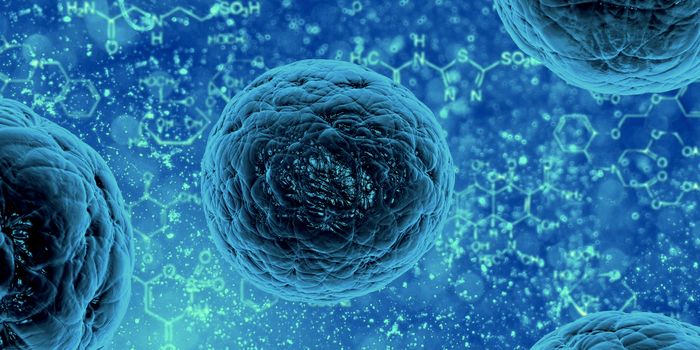

APR 02, 2024Cell & Molecular BiologyWhen a cell divides to create two new daughter cells, the process must be carefully controlled and perfectly precise, or ...